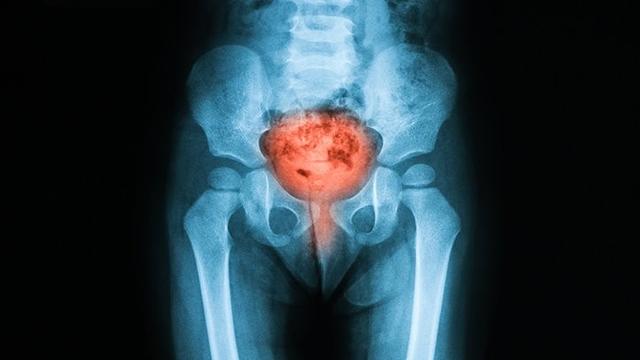

每天久坐超过5小时可能会引发尿急及其他症状

近期BJU International(英国国际泌尿外科杂志)发表了一项新研究,研究人员在两年半的时间里评估了69,795名健康中年男性,并追踪了他们每日久坐的时间,活动量以及他们是否有尿频、尿急、尿痛等下尿路症状(LUTS)。结果显示,每天久坐超过5个小时且活动量偏低的人,更容易发生LUTS,即尿不尽、尿频、尿急、晚上起夜等等。该研究仅包括男性,因此这些结果可能并不完全适用于女性,因为女性与男性有不同的尿路解剖结构(没有前列腺和尿道更短)。但我们也不能简单的假设,久坐并不